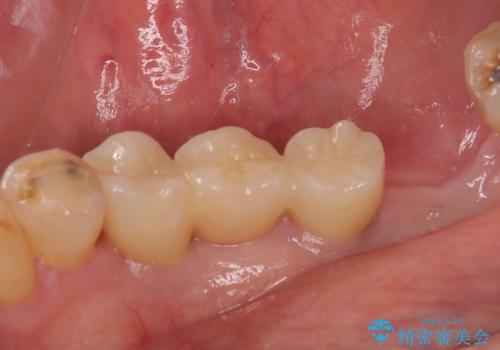

- 奥歯がなく、作ってもらった入れ歯もうまく使えないため、インプラント治療を希望して来院された患者様です。

入れ歯を装着すると咬み合わせの位置が大きく変化することが、入れ歯を使用できない理由でしたが、とにかく煩わしいのでインプラント治療を行いたいとのことでした。

インプラント埋入時に骨とインプラントの安定性を測定し、可能な限り早期に仮歯による咬合回復を図ることを前提に、インプラント補綴治療を行うこととしました。